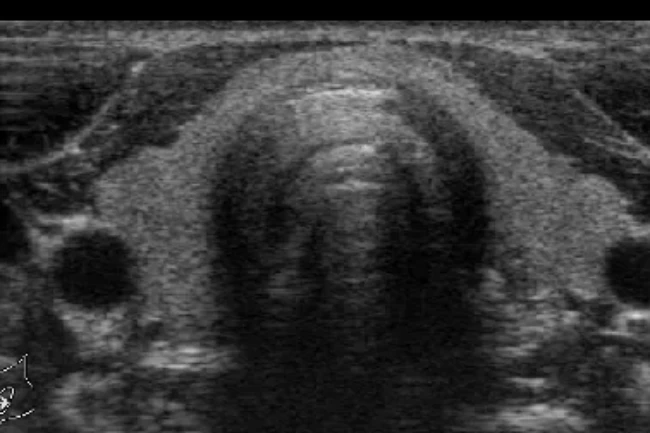

Esami ecografici a domicilio

con rilascio di referto ed immagini immediato